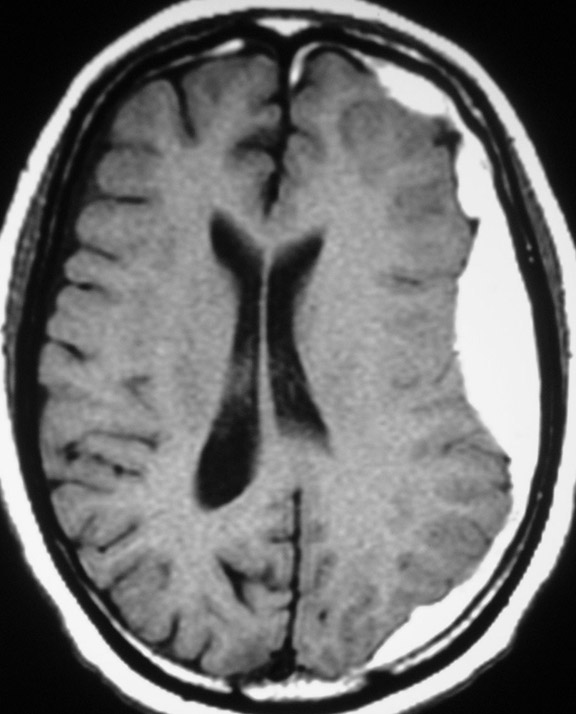

Внутрішньомозкова гематома

Цей тип гематоми розвивається при проникненні крові в головний мозок. Після травми голови можуть виникнути численні важкі внутрішньомозкові гематоми. Травма, яка призвела до появи такої гематоми, часто викликає ураження з пошкодженням білої речовини. Такі пошкодження розвиваються після того, як травма буквально розриває нейрити в білій речовині головного мозку. Нейрити - це з'єднання, що передають електричні імпульси або повідомлення від нейронів головного мозку до решти частин організму. При втраті даного з'єднання можуть з'явитися серйозні пошкодження головного мозку, тому що нейрони більше не можуть взаємодіяти.

Травма - не єдина причина внутрішньомозкових гематом.

До інших причин відносяться:

Діагностування гематоми може бути складним. Однак лікарі в основному припускають, що прогресуюча втрата свідомості після травми голови викликається крововиливом в череп, якщо не доведено інше. Кращий спосіб визначити локалізацію і розмір гематоми - це візуалізація.

- магнітно-резонансна томографія (MРТ). Зрізи МРТ отримують з використанням великого магніту і радіохвиль, які виробляють комп'ютерні зображення. Під час МРТ пацієнт лежить на рухомому столі, який вводиться в трубу або тунель.